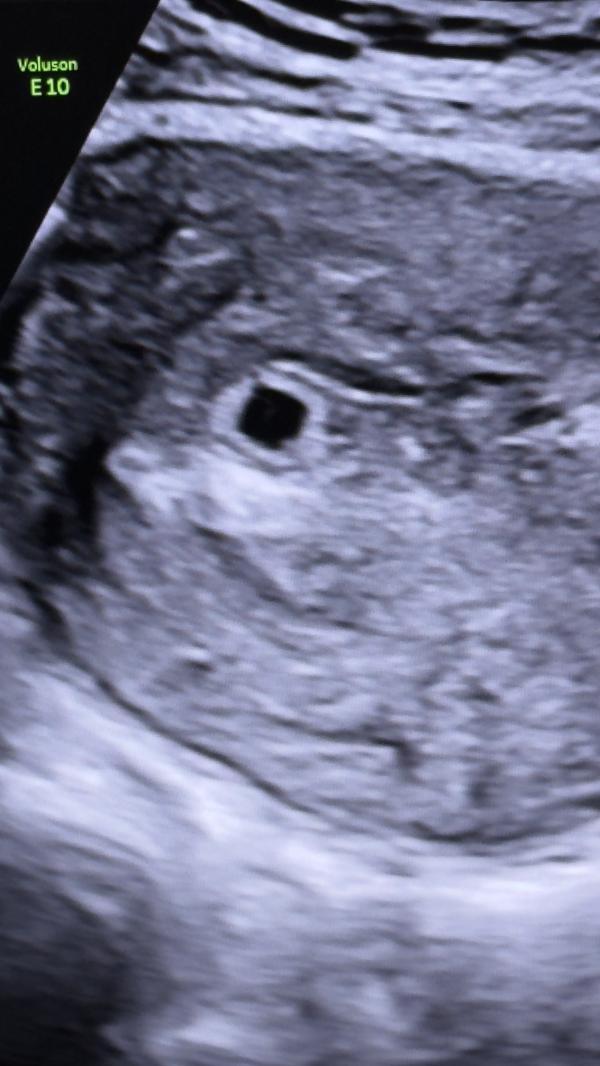

Девочки, это на фото круглое очертание разве не желточный мешок? Или я может путаю

@zarina_akimova, если это беременность, то там разве не должен быть эмбрион? Какая неделя у вас?

@seville.gadzhieva.1991, 5 недель

Сказала что срок маленький, на 4-5 недель плодное яйцо

У меня эмбрион на 6-7 нед только увидели